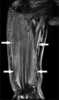

Systemic lymphoma

Hodgkin lymphoma (HL) is a type of lymphoma in which cancer originates from a specific type of white blood cells called lymphocytes. Symptoms may include fever, night sweats, and weight loss. [Source: Wikipedia ]